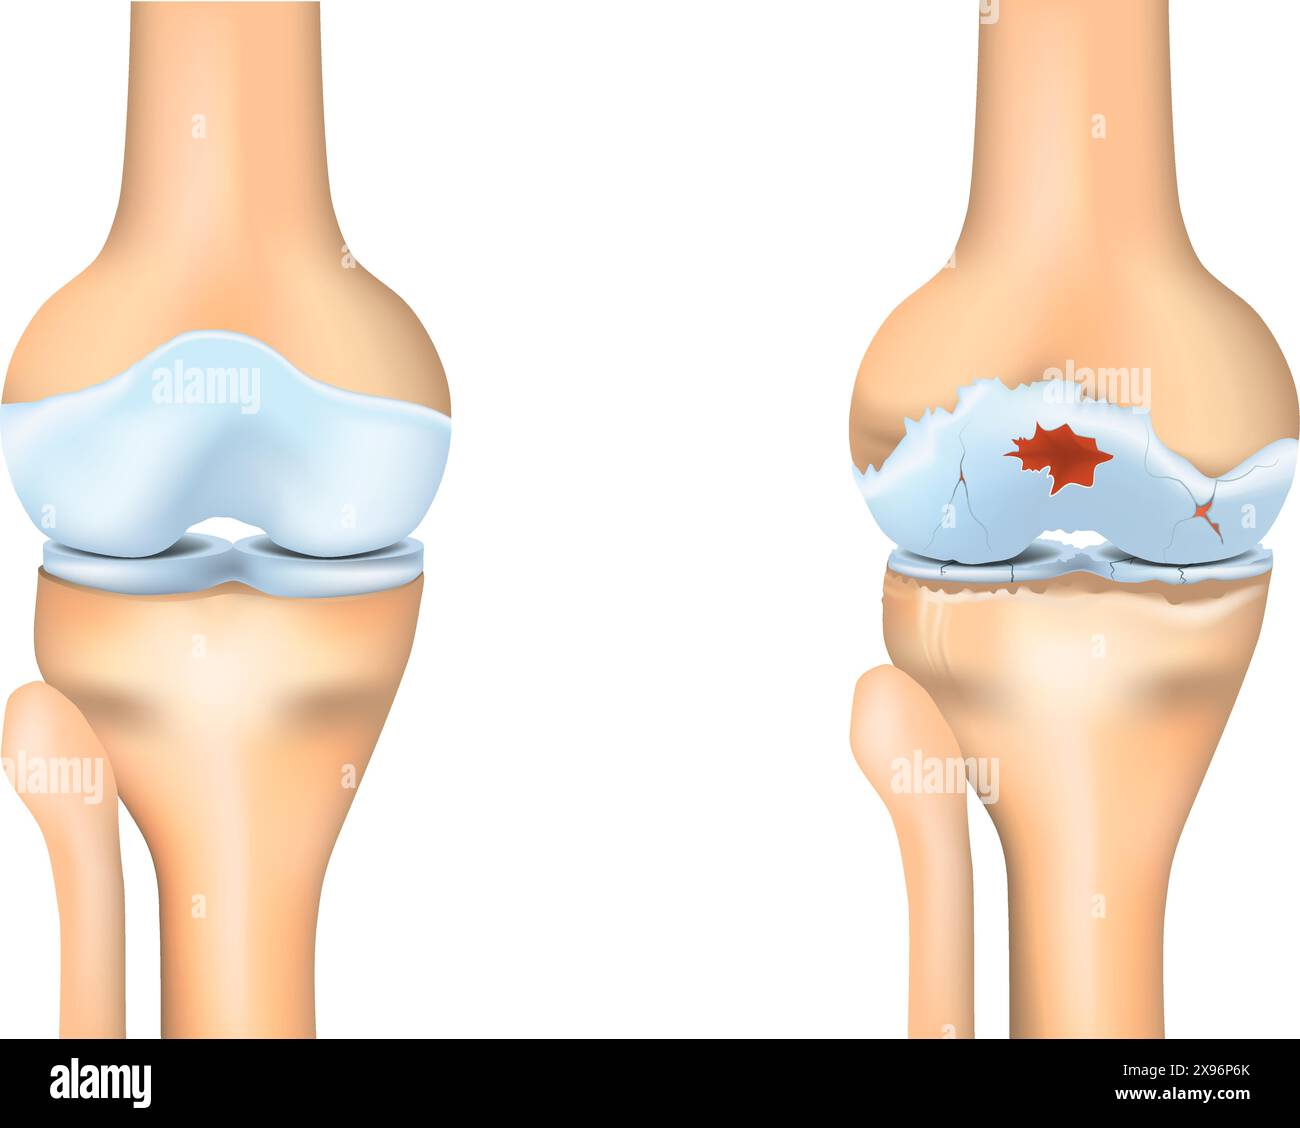

Knee osteoarthritis. Joint degeneration. Vector illustration. Stock Vectorhttps://www.alamy.com/image-license-details/?v=1https://www.alamy.com/knee-osteoarthritis-joint-degeneration-vector-illustration-image608043931.html

Knee osteoarthritis. Joint degeneration. Vector illustration. Stock Vectorhttps://www.alamy.com/image-license-details/?v=1https://www.alamy.com/knee-osteoarthritis-joint-degeneration-vector-illustration-image608043931.htmlRF2X96P6K–Knee osteoarthritis. Joint degeneration. Vector illustration.